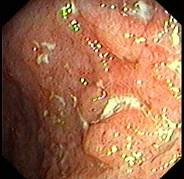

问题 女,26岁,反复右下腹疼痛4年,伴糊状腹泻,无粘液和脓血。查体:右下腹压痛,未触及包块。结肠镜检查如图,多部位活检发现炎症细胞浸润,以淋巴细胞为主,有非干酪样肉芽肿。最可能的诊断为 ( )

选项 A.溃疡性结肠炎 B.Crohn病 C.肠结核 D.慢性阑尾炎 E.细菌性痢疾

答案 B